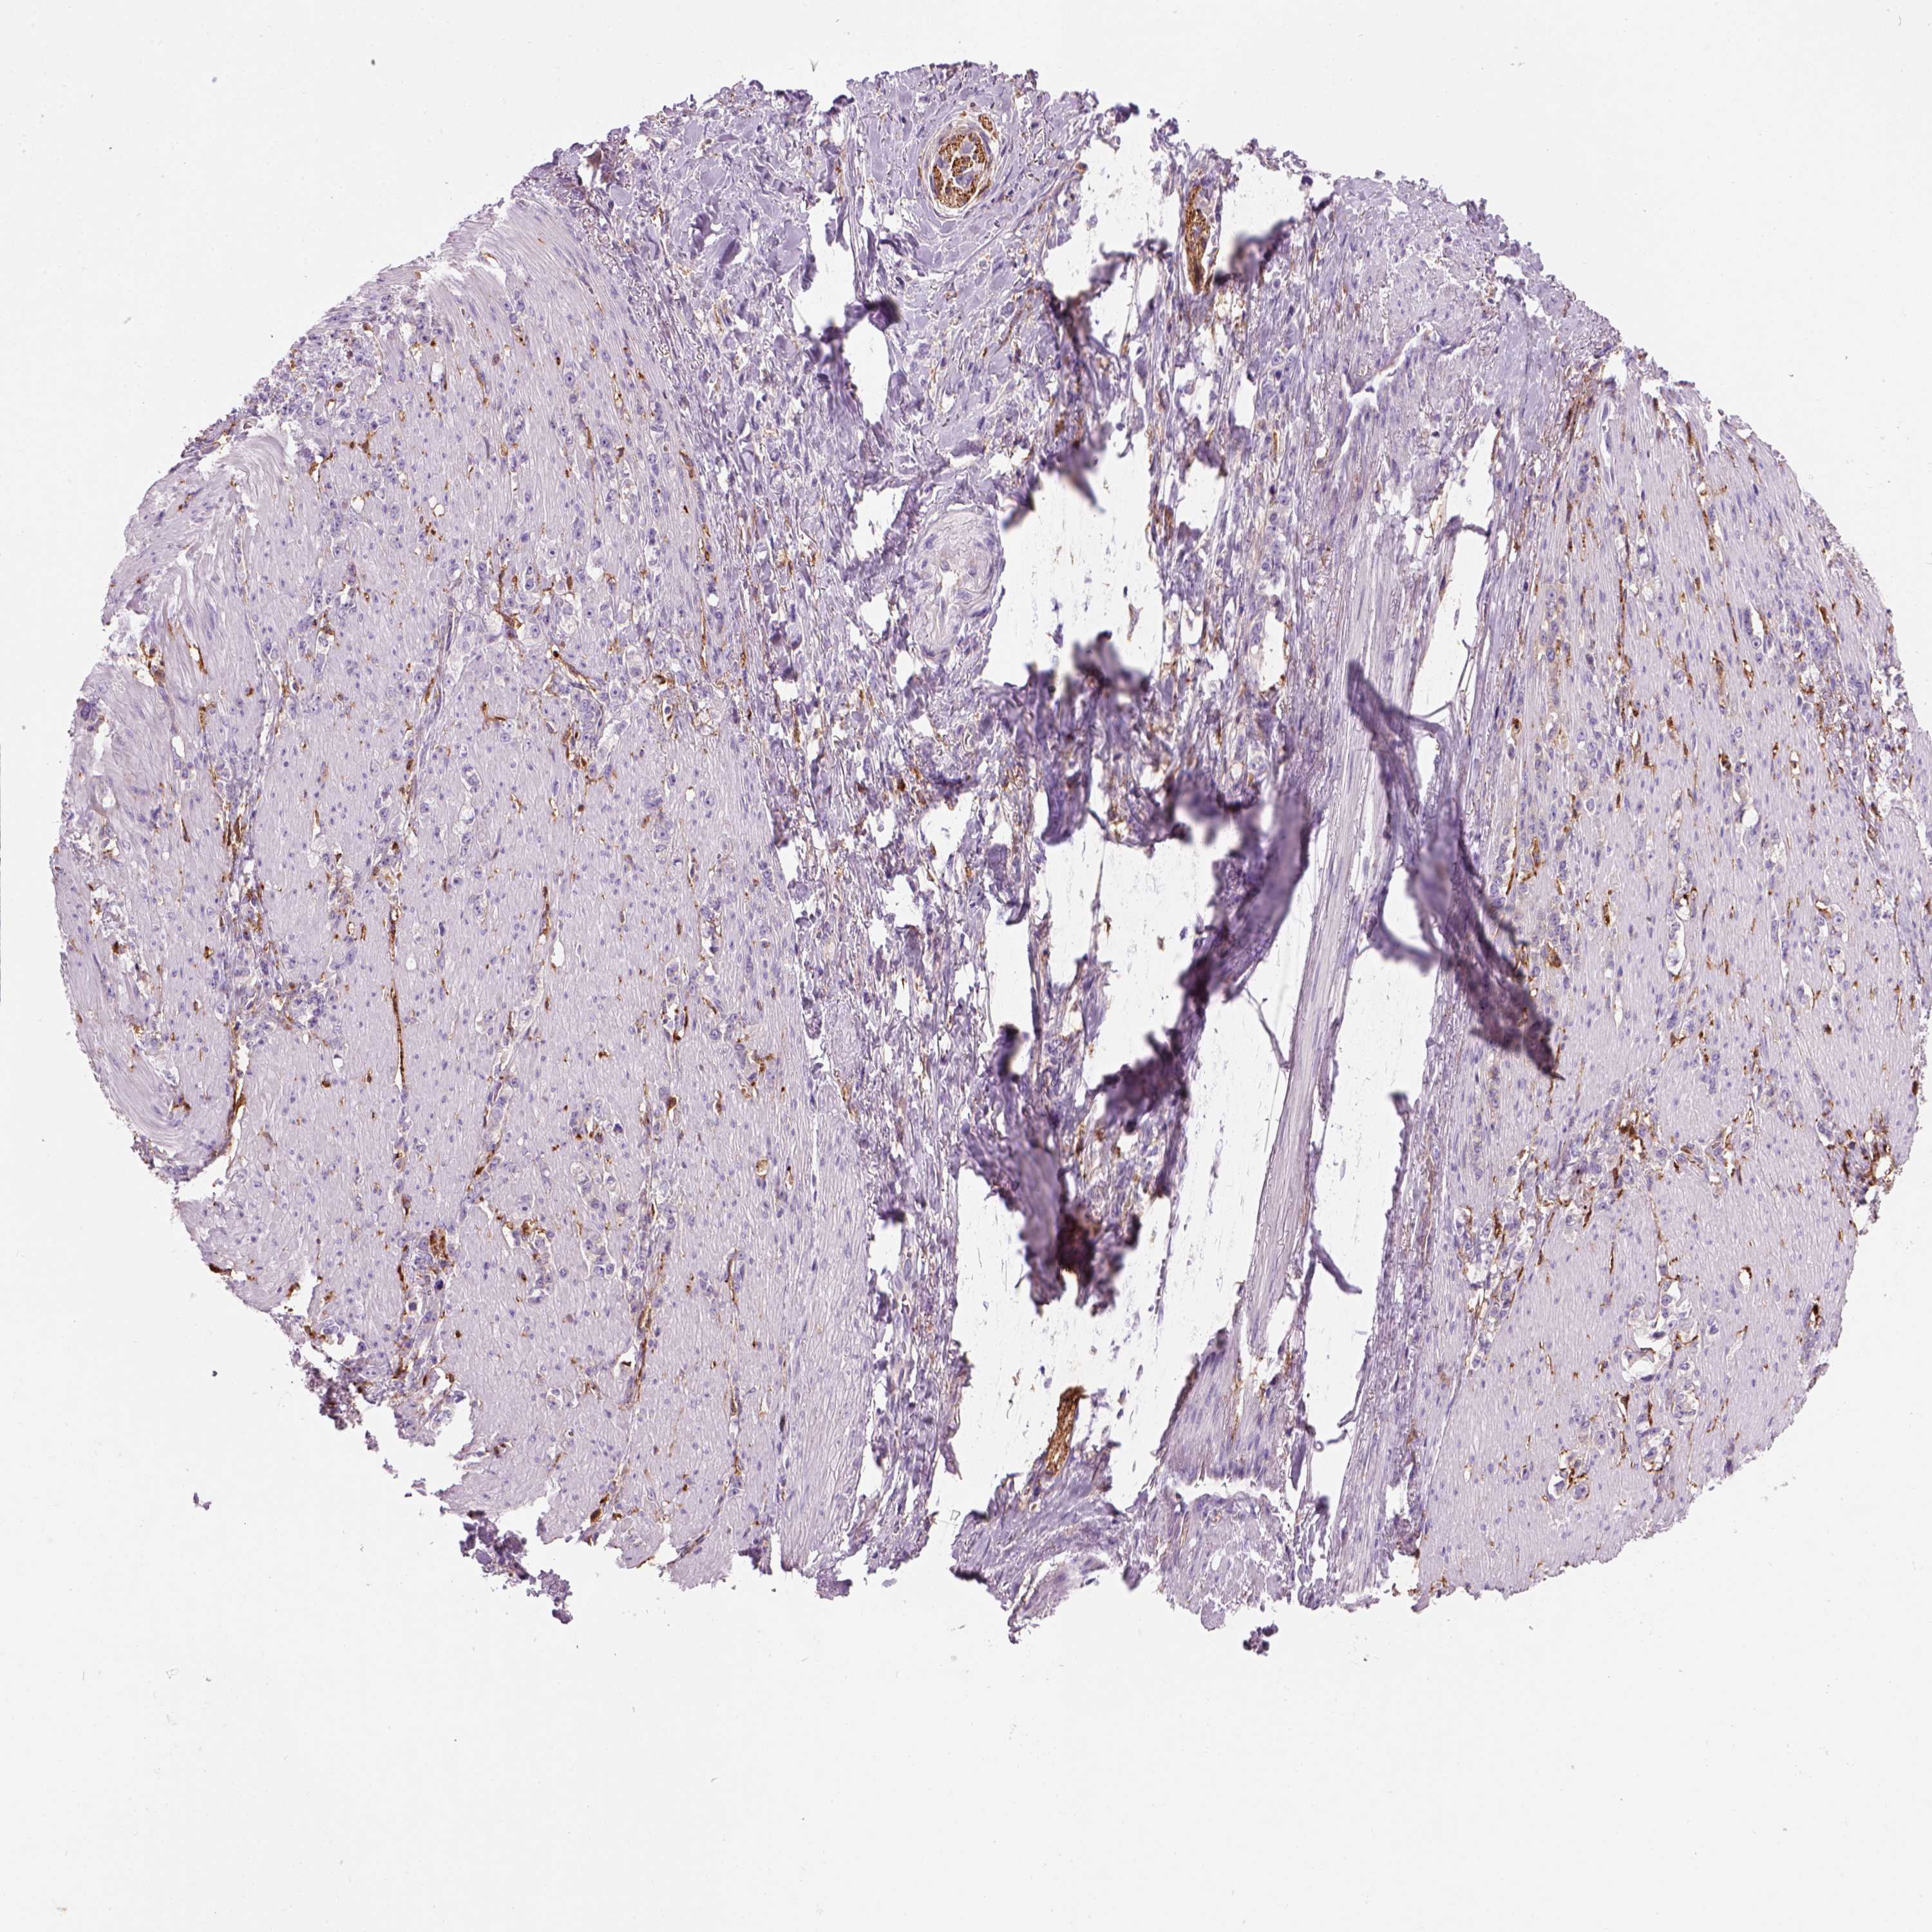

STOMACH CANCER - Protein expressioni

A mouse-over function shows sample information and annotation data. Click on an image to view it in a full screen mode. Samples can be filtered based on level of antibody staining by selecting one or several of the following categories: high, medium, low and not detected. The assay and annotation is described here.

Note that samples used for immunohistochemistry by the Human Protein Atlas do not correspond to samples in the TCGA dataset.

Antibody stainingi

Antibody staining in the annotated cell types in the current human tissue is reported as not detected, low, medium, or high, based on conventional immunohistochemistry profiling in selected tissues. This score is based on the combination of the staining intensity and fraction of stained cells.

Each image is clickable and will lead to virtual microscopy that enables deeper exploration of all samples and also displays staining intensity scores, fraction scores and subcellular localization as well as patient and tissue information for each sample.

Antibody HPA067595

Antibody HPA069443

Antibody CAB022062

Staining

High

Medium

Low

Not detected

Intensity

Strong

Moderate

Weak

Negative

Quantity

>75%

75%-25%

<25%

None

Location

Nuclear

Cytoplasmic/membranous

Cytoplasmic/membranous,nuclear

Adenocarcinoma, NOS

Adenocarcinoma, High grade